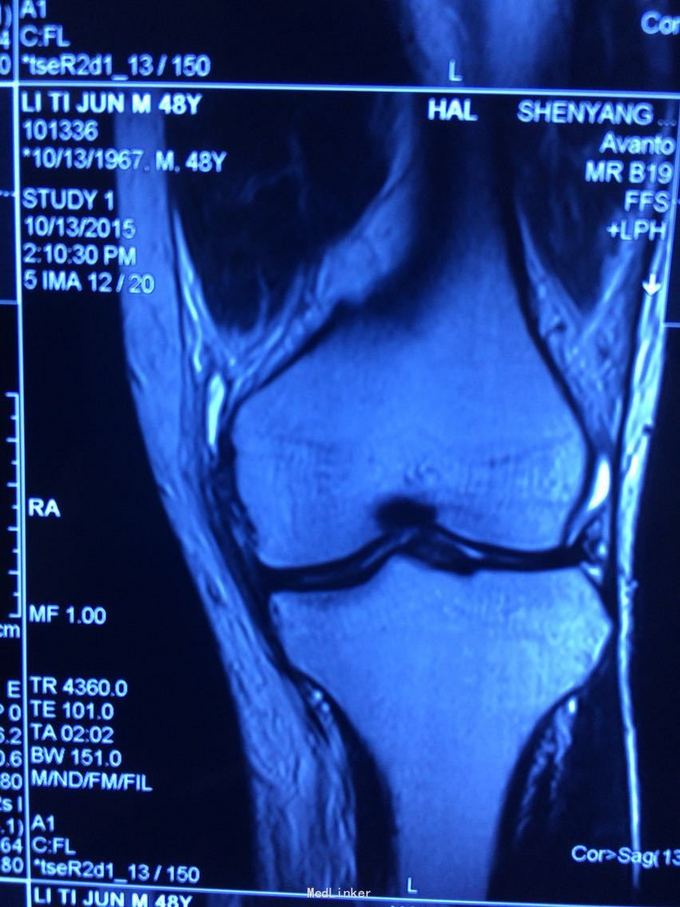

交通伤后膝关节疼痛,关节不稳。 患者交通伤,膝关节肿胀、疼痛,活动受限,肿胀消退后关节不稳。

查体:髌骨稳定,拉赫曼试验阴性,台阶征阳性3+,拨号征阴性,外翻0度阴性、30度阳性,内翻阴性。

诊断:膝关节多发韧带损伤,后交叉韧带、内侧副韧带 处理:给予关节镜下后交叉韧带重建,小切口修补内侧副韧带,取自体半腱股薄肌腱